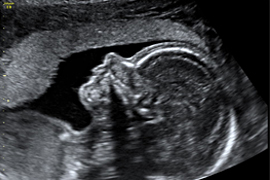

Schon gegen Ende des ersten Schwangerschaftsdrittels sind alle kindlichen Organe angelegt. Auch wenn Sie keine Untersuchung zur Vorhersage des Risikos für eine genetische Veränderung (I. Trimesterscreening s.o.) wünschen, ist eine frühe Darstellung der Organe des Embryos sinnvoll, da hier schon viele schwere Entwicklungsstörungen ausgeschlossen werden können.

Zum jetzigen Zeitpunkt können bereits Gehirn, Herz, Zwerchfell, Magen, Bauchwand und Harntrakt sowie die Kopfkontur und die Extremitäten dargestellt werden. Einen „großen Ultraschall“ im 2. Drittel der Schwangerschaft kann diese Untersuchung allerdings noch nicht ersetzen.

Eine Ultraschalluntersuchung kann jedoch nie alle körperlichen Auffälligkeiten oder Entwicklungsstörungen und genetische Fehlanlagen aufdecken.